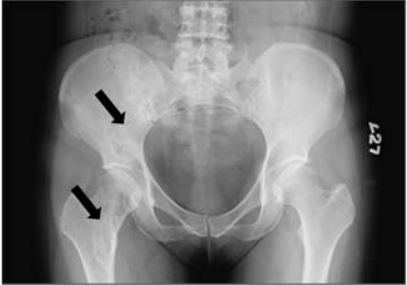

73.51歲女性病人主訴右髖關節疼痛約3週,附圖為骨盆X光片,箭號所指處最可能的診斷為:

(A)fibrous dysplasia(B)bone metastasis(C)chondrosarcoma(D)osteosarcoma